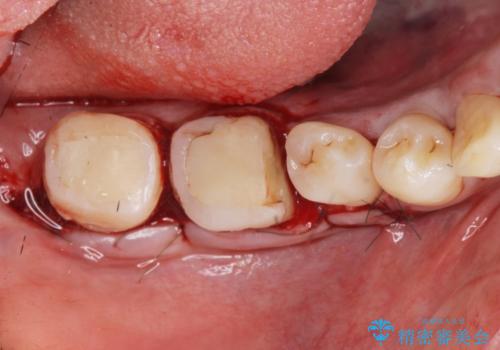

{ 歯周外科 } 骨隆起除去を含む歯冠長延長術

奥歯は既に根管治療が為されクラウンを装着する必要性がある状態ですが、歯の高さが低くクラウンの安定性・強度を担保するために歯周外科を行う治療計画としました。

歯周外科を行うことで、歯ぐきの位置を下げ歯の高さを作り出し安定したクラウンの装着が可能となります。また同時に舌の邪魔となっていた骨隆起の除去を行うこととしました。